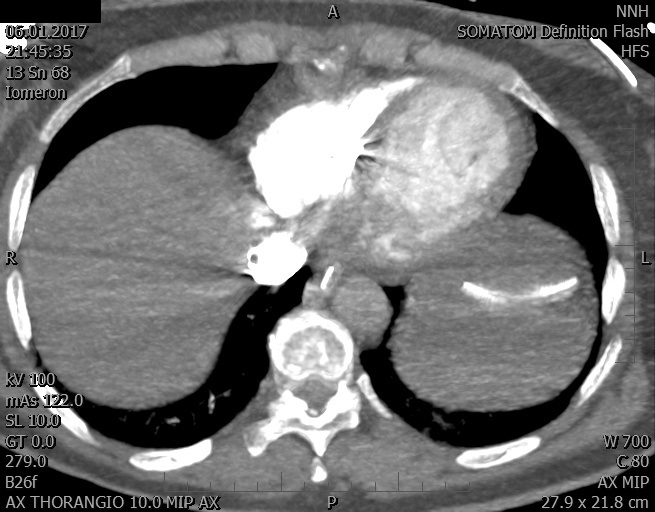

Video 1 - Akutní koronarografie prokázala normální nález na věnčitých tepnách s výjimkou suspekce na lehký spasmus na pravé koronární tepně.Echokardiograficky byla zjištěna těžká dysfunkce dilatované levé komory s nezvětšenou pravou komorou (video 2).

Video 2 - Echokardiograficky byla zjištěna těžká dysfunkce dilatační levé komory s nezvětšenou pravou komorou.Pro nejasnou příčinu zástavy jsme provedli i vyšetření výpočetní tomografií (CT), které vyloučilo plicní embolizaci (série 1 - soubory na konci článku). V den přijetí při přetrvávající oběhové nestabilitě byla nemocná opakovaně defibrilována pro fibrilaci komor se stabilizací rytmu po podání amiodaronu a mesocainu. Dle hemodynamických měření se jednalo o těžký kombinovaný šok. Vstupní laboratorní vyšetření bylo bez větších pozoruhodností. Posléze jsme doplnili anamnézu od příbuzných a zjistili, že pacientka užila do dvou hodin před srdeční zástavou první tabletu amoxicilinu na lehký respirační infekt. Při nevýtěžnosti vstupních vyšetření a nových anamnestických informacích jsme doplnili 14 hodin po kolapsu vyšetření koncentrace tryptázy v séru, která byla extrémně zvýšena (tabulka 2), což nás vedlo k podezření na anafylaxi.